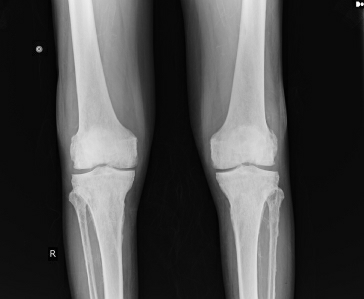

Examination Of Joints

Knee & ankle joint : Unable to flex completely , but can flex upto 30 degrees

Swelling + , Stiffness +